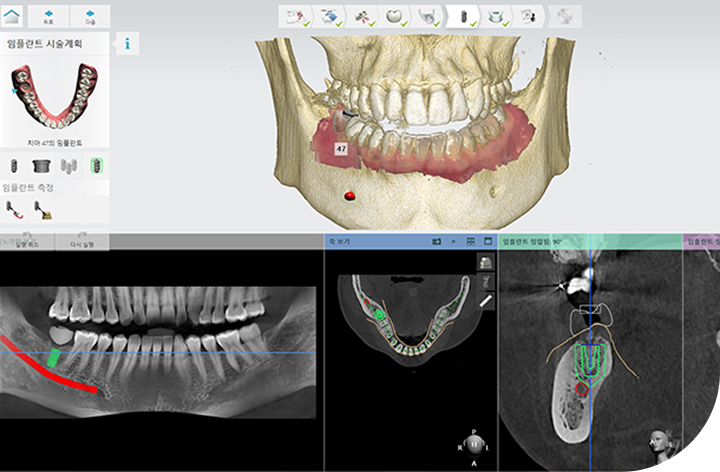

환자의 구강 정보를 디지털 데이터를 기반으로 3D 가상 모의 수술을

진행해 기존 방식 대비 수술 시간이 짧아 체력적 부담을 줄여주고

최소 절개로 통증 및 붓기 최소화로 면역력이 약하거나 회복력이 더딘

고령의 환자, 고혈압 당뇨 등 전신질환을 앓고 계신 분들도 부담없이 안전하게 수술받을 수 있습니다.

3D-CT를 통한 정밀 진단

3D-CT 분석을 통해 상악동 구조와

골 상태를 정확하게 진단합니다.